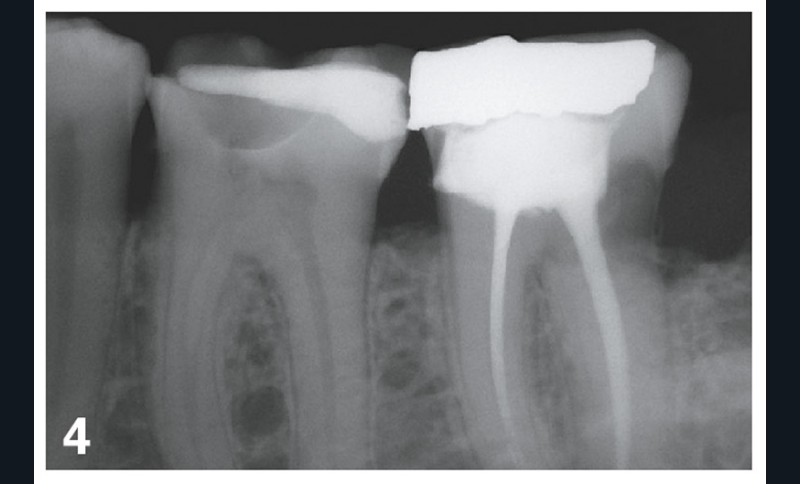

Dans le cas illustré par les figures 1 à 4 ci-dessus, les 16, 17 et 36 doivent être soignées et restaurées. Le choix des onlays permet :

– une solution économe en tissus dentaires ;

– une liberté d’honoraires ;

Le choix de trois couronnes périphériques aurait nécessité de présenter au moins une alternative en RAC-0, en l’occurrence des couronnes métalliques. Bien entendu, de nombreux patients auraient refusé et auraient choisi une option plus esthétique. Les honoraires auraient cependant été plafonnés pour cette option RAC-0.